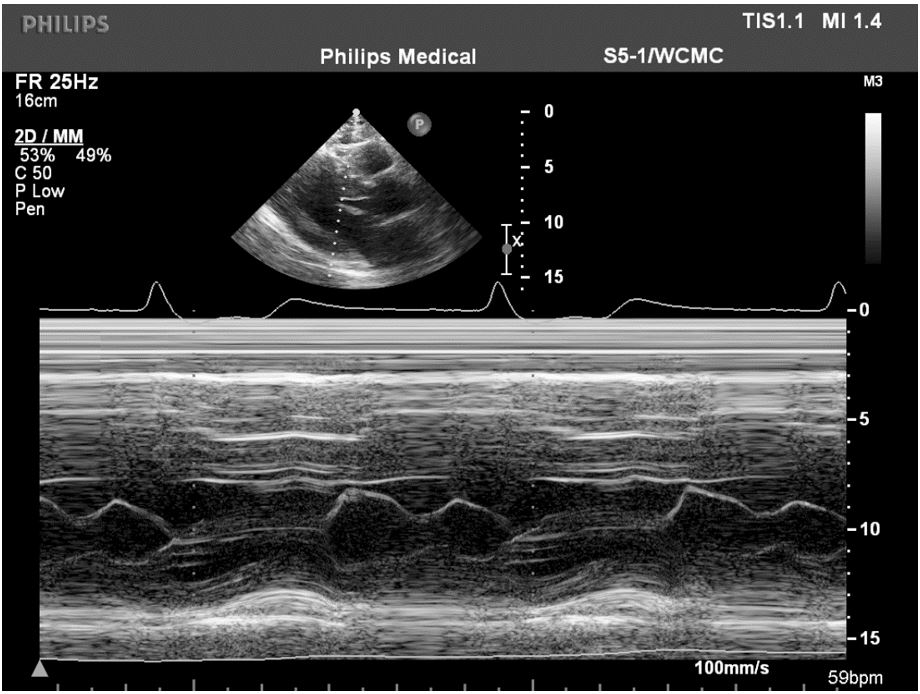

A 47-year-old man with hypertension, hyperlipidemia, and hypertrophic obstructive cardiomyopathy (HOCM) treated with atenolol and verapamil to maximally tolerated doses reports worsening dyspnea on exertion. He has a history of mild-to-moderate mitral regurgitation (MR) with a resting left ventricular outflow tract (LVOT) peak gradient of 49 mmHg (Figure 1), provokable to 60 mmHg with exercise. On exam, his blood pressure is 125/80 mmHg with a resting heart rate of 53 bpm. He has a III/VI harsh mid-systolic murmur at the left lower sternal border and a II/VI mid-systolic murmur at the apex. Disopyramide therapy is aborted due to excessive QT prolongation. An echocardiogram demonstrates a septal thickness of 2.0 cm, a normal ejection fraction of 66%, and systolic anterior motion of the mitral leaflets with 4+ severe MR and 1+ mild aortic regurgitation (Figure 2, Videos 1-3). Cardiac magnetic resonance imaging confirms these findings along with severe left atrial enlargement and anterior displacement of the anterior papillary muscle (Figure 3, Video 4).

Figure 1